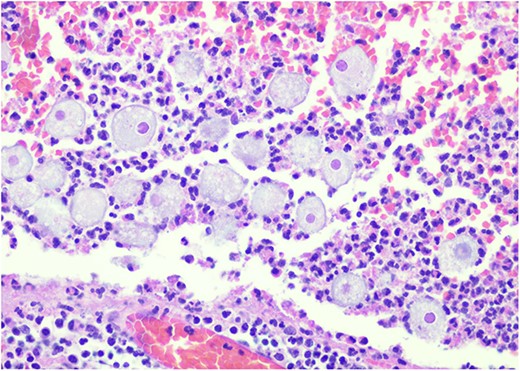

Pathology resulted on post-operative day three showing an inflamed appendix, 1.4 cm in diameter, with an exudative-filled lumen. On microscopic stains, there was evidence of acute appendicitis with frequent scattered unicellular organisms within areas of ulcerated appendiceal mucosa and submucosa (Figs 6 and 7). These cellular forms have round cell membranes, single prominent round eosinophilic nuclei and foamy cytoplasm (Fig. 5). Occasional forms show evidence of erythrophagocytosis (Fig. 3). Forms were also highlighted by trichrome and PAS special stains (block A1) and were negative for CD68 (a marker of macrophages; block A1) (Figs 2–4). These morphologic features are most consistent with E. histolytica, which is a pathogenic parasite in the lower GI tract, and likely the causative agent for acute appendicitis in this case.

H&E 200X—unicellular parasites within submucosal tissue with inflammation.